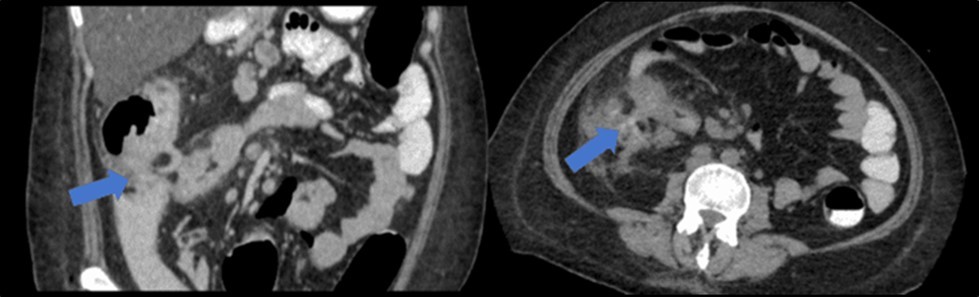

There was no evidence of malignancy or IBD seen during both endoscopic procedures. Computed tomography (CT) scan of the whole abdomen was done which showed inflammatory changes involving the cecum and adjacent duodenum and ileum with coloenteric fistulae. There was noted progression of abdominal lymphadenopathies as well as ascites. Main consideration was an infectious disease process (i.e. TB) (Figure 2, Figure 3, Figure 4 to Figure 5).

Figure 2.Colonoscopy finding of a circumferential, obstructive and nodular mass with areas of necrosis with a pathologic lumen believed to be communicating with the lumen seen on the previous EGD was seen at the proximal transverse which precluded further advancement of the scope